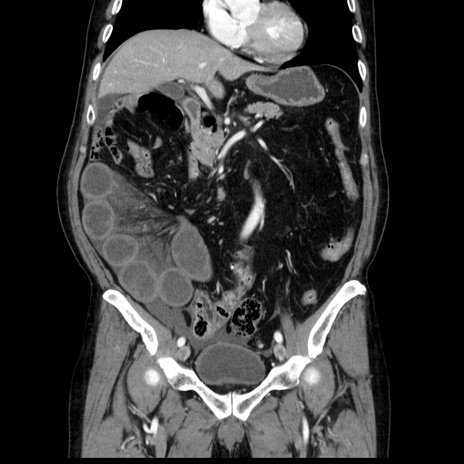

症例30(冠状断像)

【症例】80歳代男性

【主訴】臍周囲痛

【現病歴】約6時間前から臍下部痛が出現。次第に腹部膨隆・背部痛も生じてきたため来院。背部痛の場所は変化しない。

【身体所見】意識清明、BT 36.3℃、BP  131/87mmHg、P 87bpm、SpO2 100%(RA)、臍周囲自発痛・圧痛あり、反跳痛なし、自発痛部位に一致して板状硬あり、腹部膨隆、腸雑音減弱、CVA tenderness両側陰性。

【データ】WBC 19600、CRP 0.33

横断像